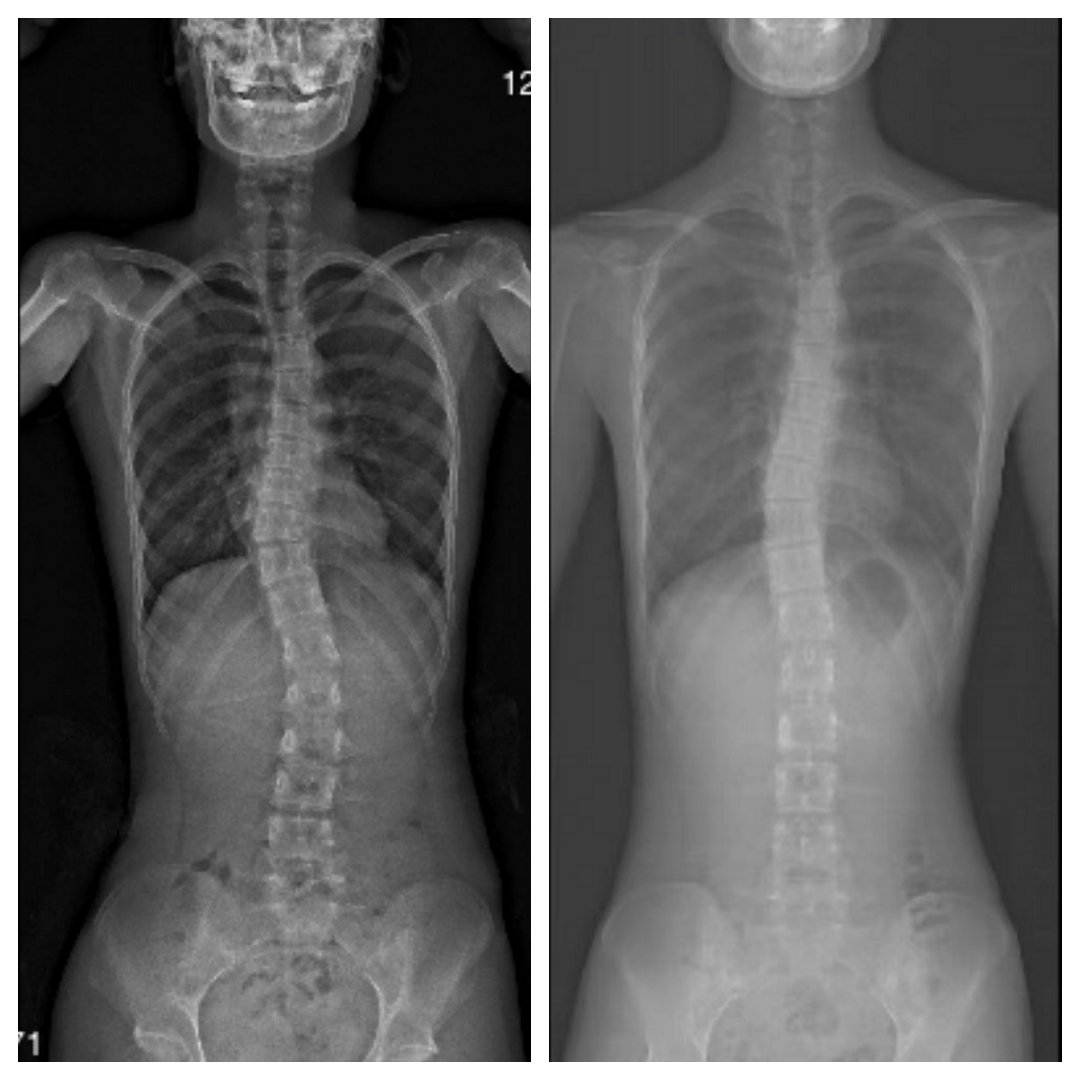

一张X光片胜过千言万语

经过数月的努力,我们再次拍摄X光片。结果令人振奋——变化清晰可见!

说明:惊人改善!侧弯角度(Cobb角)明显缩小,脊柱排列显著优化。

– 脊柱侧弯Cobb角明显下降(主要评估指标)

– 双肩、骨盆更加水平对称